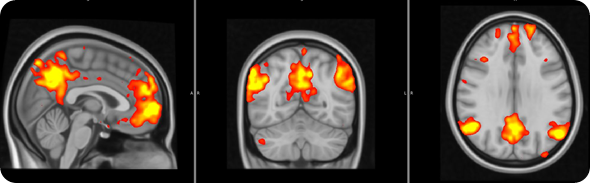

In this study brain activity was investigated when the participants received painful stimuli, as well as when they received visual cues informing the subjects of impending pain onset (pain anticipation) and pain offset (relief anticipation).

We saw that the healthy subjects showed large brain responses, in many regions, when they were anticipating pain or relief. Some of these changes are likely to be due to the detection of ‘salient’ event. In other words, some of these responses may be non pain-specific and may simply reflect the fact that the subjects were detecting an ‘interesting event’.

However, other responses would seem to be even more interesting, and possibly pain specific: for instance the healthy volunteers activated a region called the ‘periaqueductal gray region’, which we know exerts a modulatory effect on the pain signals coming to the periphery (this is a region that if stimulated electrically can alleviate pain).

The healthy volunteers also showed that a region involved in the processing of ‘reward’/’punishment’, the so called ventral tegmental area (VTA), was activated during pain anticipation, and deactivated during relief anticipation.

FM patients exhibited reduced brain responses in response to visual cues for both pain anticipation as well as relief anticipation.

This reduced responsiveness was very widespread, and included the periaqueductal gray and the VTA.